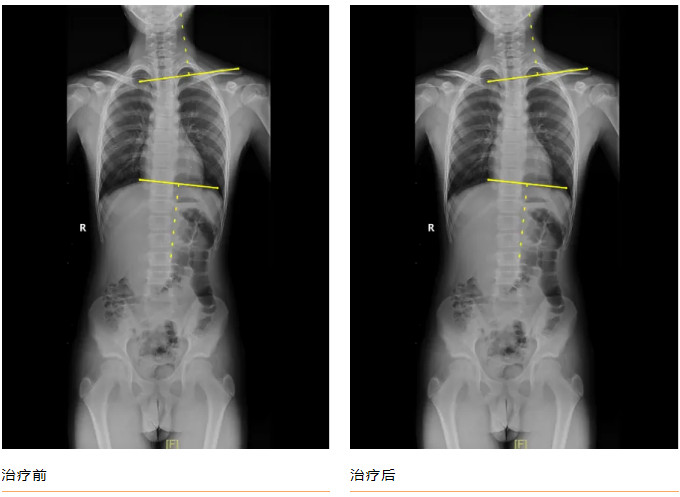

青少年小黄(化名),11岁,家属发现脊柱异常1年余。查体:双下肢真性长度等长,前屈试验阳性,ATR≥5°。全脊柱正侧位片示:“胸椎右侧弯畸形,Cobb角= 23.44 °”。

黄播 康复医学科诊疗团队诊断:“特发性脊柱侧弯”,为小黄制定完善的康复方案:一、脊柱侧弯健康宣教,二、基础运动训练(猫卷式、四点撑抗阻脊柱核心训练、侧平板、胸廓打开训练),三、传统康复训练(牵伸治疗、稳定性训练),柱侧弯得到明显矫正,复查全脊柱正侧位片示:“胸椎右侧弯畸形,Cobb角= 13.45 °”